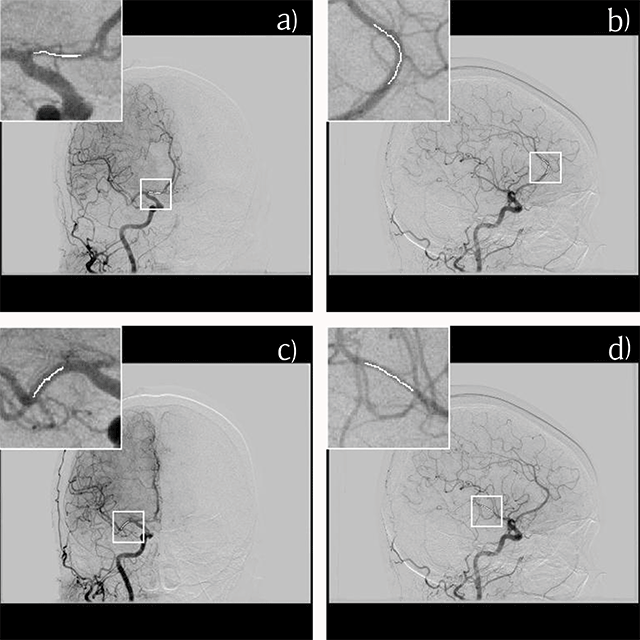

Figure 1

Measurement of contrast enhancement for the A1 (a), A2 (b), M1 (c) and M2 (d) segments on the source rotational two-dimensional digital subtraction angiography. The pixel value at the center of the projected vessel is extracted manually, and the average value on several images is calculated.